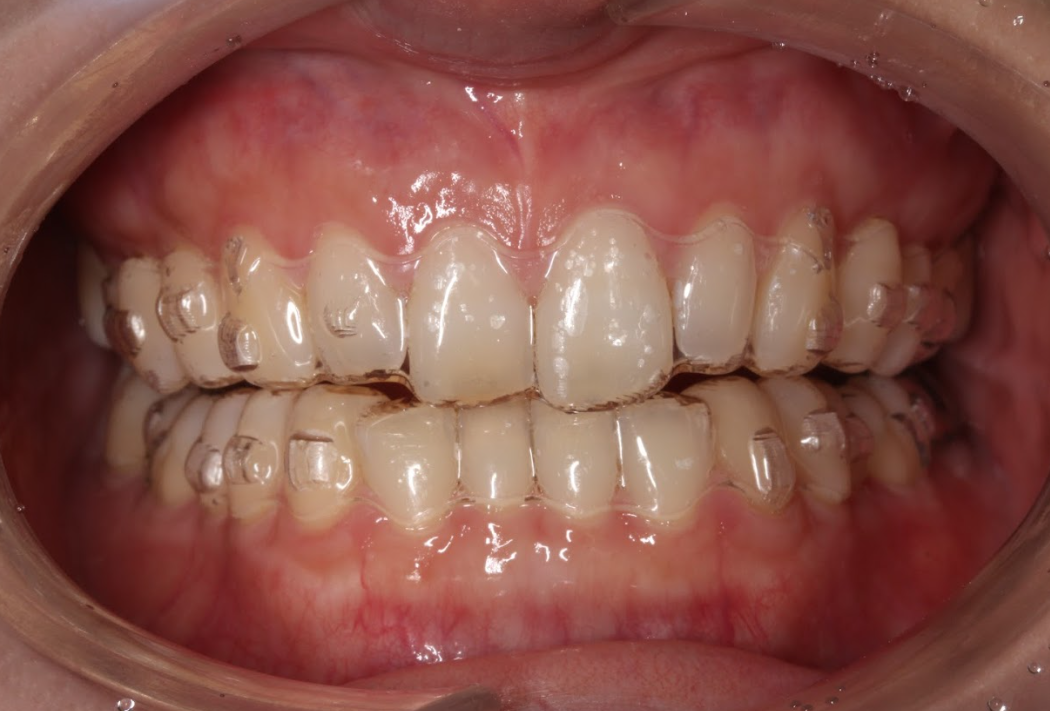

【バイトランプ使用時の正面観・前歯部あおり】